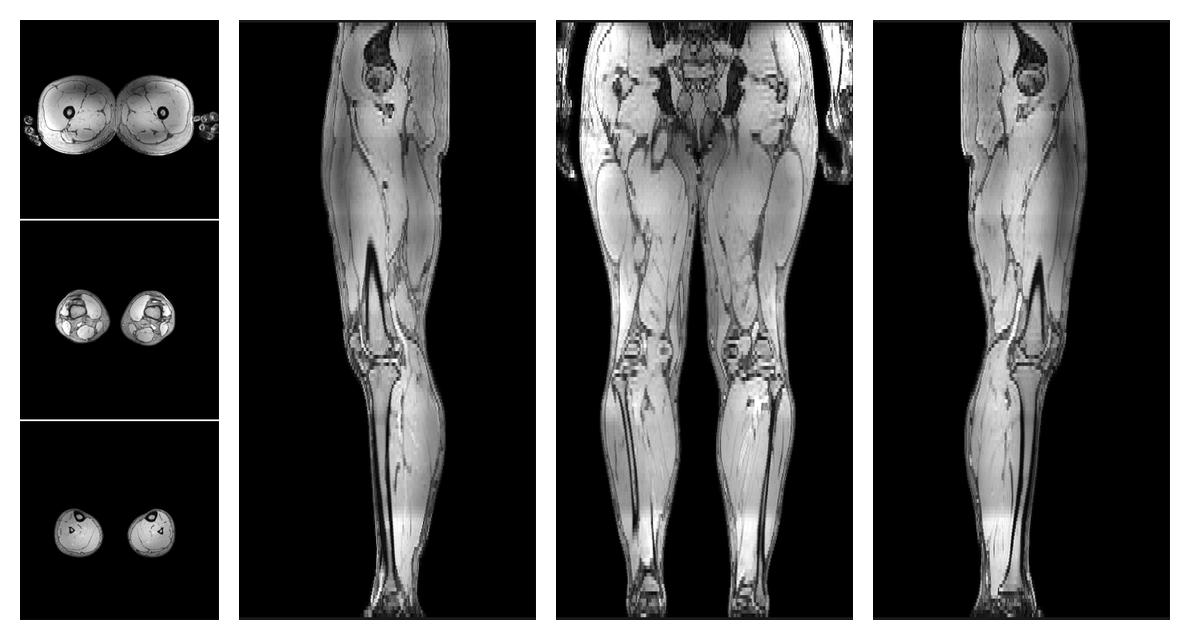

• Automated muscle and bone segmentation.

Overlay of automated muscle segmentation labels on dixon water image.